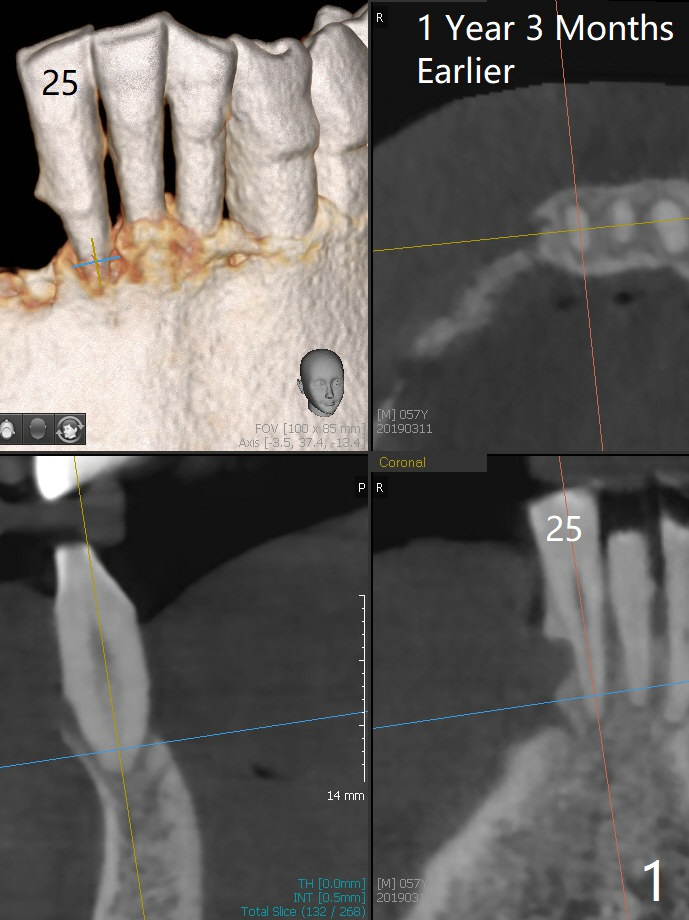

The 58-year-old man returns for #25 extraction while the redo implant at #12 is osteointegrating (Fig.1-3). After discussion, he agrees with socket preservation with 8x8 mm BioXclude (Fig.4 * (4-0 PGA)) and Vanilla graft (Fig.5 *). The socket is healing 6 days postop (Fig.6).